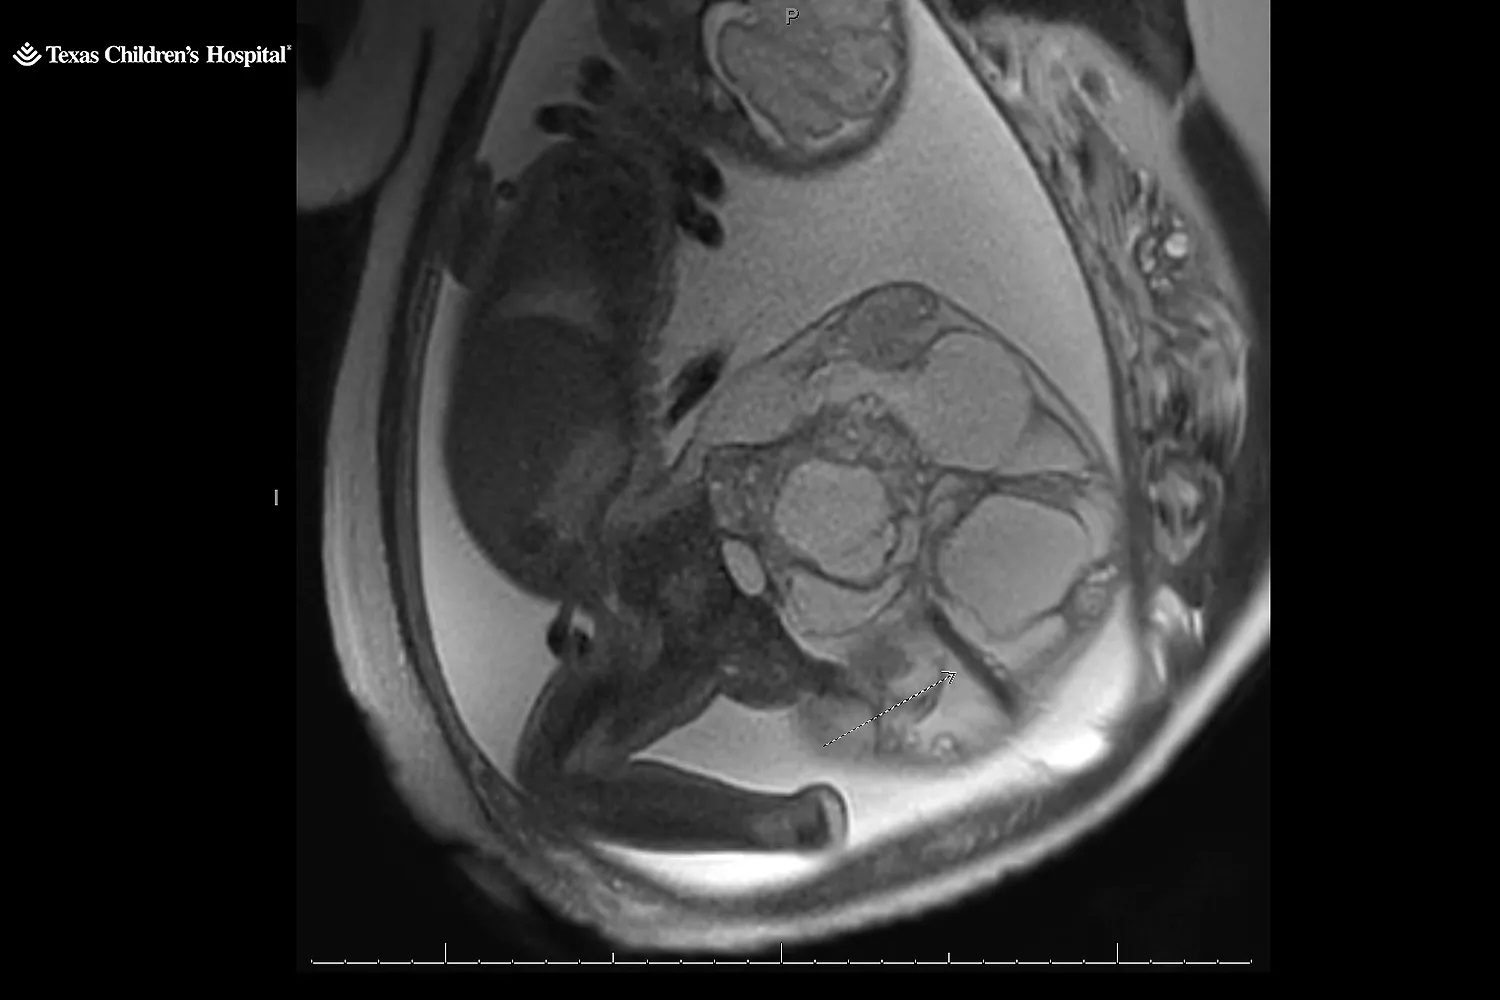

Την επόμενη μέρα, ένας ειδικός διέγνωσε ότι το κοριτσάκι τους δεν είχε δισχιδή ράχη, αλλά ένα σπάνιο εμβρυϊκό όγκο, το ιεροκοκκυγικό τεράτωμα, που σχηματίζεται από τον κόκκυγα του μωρού. Το ιεροκοκκυγικό τεράτωμα εμφανίζεται σε μία στις 20.000 γεννήσεις. Το ζευγάρι παραπέμφθηκε στο Texas Children’s Pavilion for Women στο Χιούστον για να παρακολουθείται από εξειδικευμένη ιατρική ομάδα.

Ταξίδεψαν σχεδόν 400 χιλιόμετρα από το σπίτι τους για να συναντήσουν τον Dr. Ahmed Nassr, ειδικό σε εμβρυομητρική ιατρική και χειρουργό στο Texas Children’s Pavilion for Women. Ο Nassr τους εξήγησε ότι ο όγκος ήταν «πολύ σπάνιος». Μάθανε ότι εμφανίζεται συχνότερα σε κορίτσια παρά σε αγόρια και ότι συνήθως είναι καλοήθης. Ωστόσο, οι γιατροί δεν γνωρίζουν πάντα γιατί συμβαίνει.

«Είναι απλώς κακή τύχη», λέει ο Nassr. Οι όγκοι αυτοί μπορούν να γίνουν πολύ μεγάλοι και, καθώς αναπτύσσονται, μπορεί να δημιουργήσουν μεγάλα αιμοφόρα αγγεία. «Στην ουσία κλέβουν από το μωρό το αίμα που χρειάζεται», εξηγεί ο Nassr. «Η καρδιά του μωρού πρέπει να δουλέψει πολύ σκληρά» για να ανταποκριθεί, κάτι που μπορεί να οδηγήσει σε καρδιακή ανεπάρκεια.

Στις 21 Μαΐου, στις 34 εβδομάδες, η Kristin γέννησε με καισαρική. Η μικρή Adalida γεννήθηκε με έναν όγκο 16 εκατοστών, που ζύγιζε περίπου 1,8 κιλά – σχεδόν τα δύο τρίτα του σωματικού της βάρους.

Συνολικά, το μωρό και ο όγκος ζύγιζαν πάνω από 4,5 κιλά. Ο Nassr περιγράφει το μέγεθος του όγκου ως «λίγο μικρότερο από ένα καρπούζι, αλλά μεγαλύτερο από ένα πεπόνι». «Ήταν ένας μεγάλος όγκος, γι’ αυτό ανησυχούσαμε τόσο πολύ», λέει.